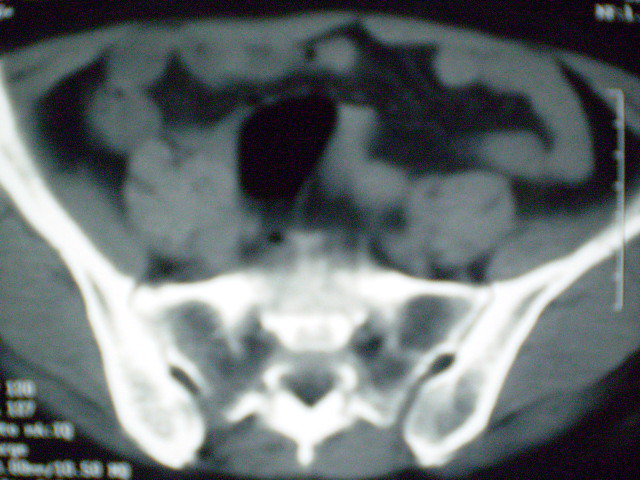

f 60y,b超提示脂肪瘤.[img][/img]

右侧附件囊性畸胎瘤,三种组织均见.

的确比较典型的畸胎瘤!不过,应该确切的说是盆腔畸胎瘤,右侧附件来源的可能性比较大。